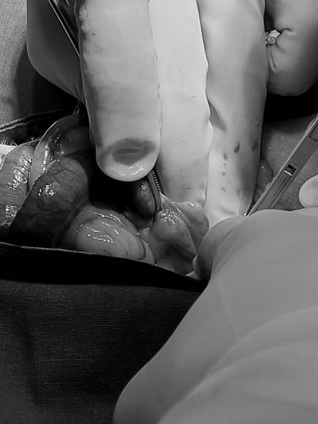

자궁노출 → 좌자궁각 및 난소절제 → 좌자궁각 혈관결찰

오른쪽 축 자궁각 혈관결 → 오른쪽 자궁각 및 난소절제 → 양쪽 자궁각 및 난소절제 후

호흡 마취 후 개복하여 양쪽 난소 및 자궁을 제거하였습니다.